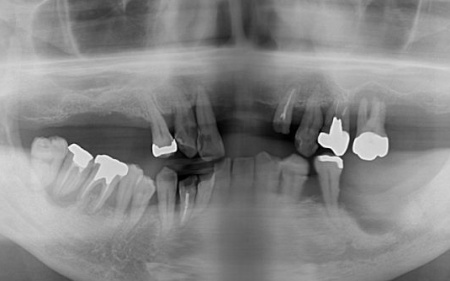

また、患者様は重度の歯周病によって歯を支える骨が減少し全体的に歯が揺れていました。

残っている上の歯7本(左右上側切歯、左右上犬歯、左右上第1小臼歯、左上第1大臼歯)と右下奥歯2本(第2大臼歯、第3大臼歯)は残すことが難しく抜歯が必要な状態です。

以上のことから、抜歯を行ったうえで歯を補う治療が必要と診断しました。

インプラント治療が可能かどうかを調べるためレントゲンとCTの撮影を実施したところ、インプラントを支えるのに十分な骨の量があり問題なく治療できることが確認できました。